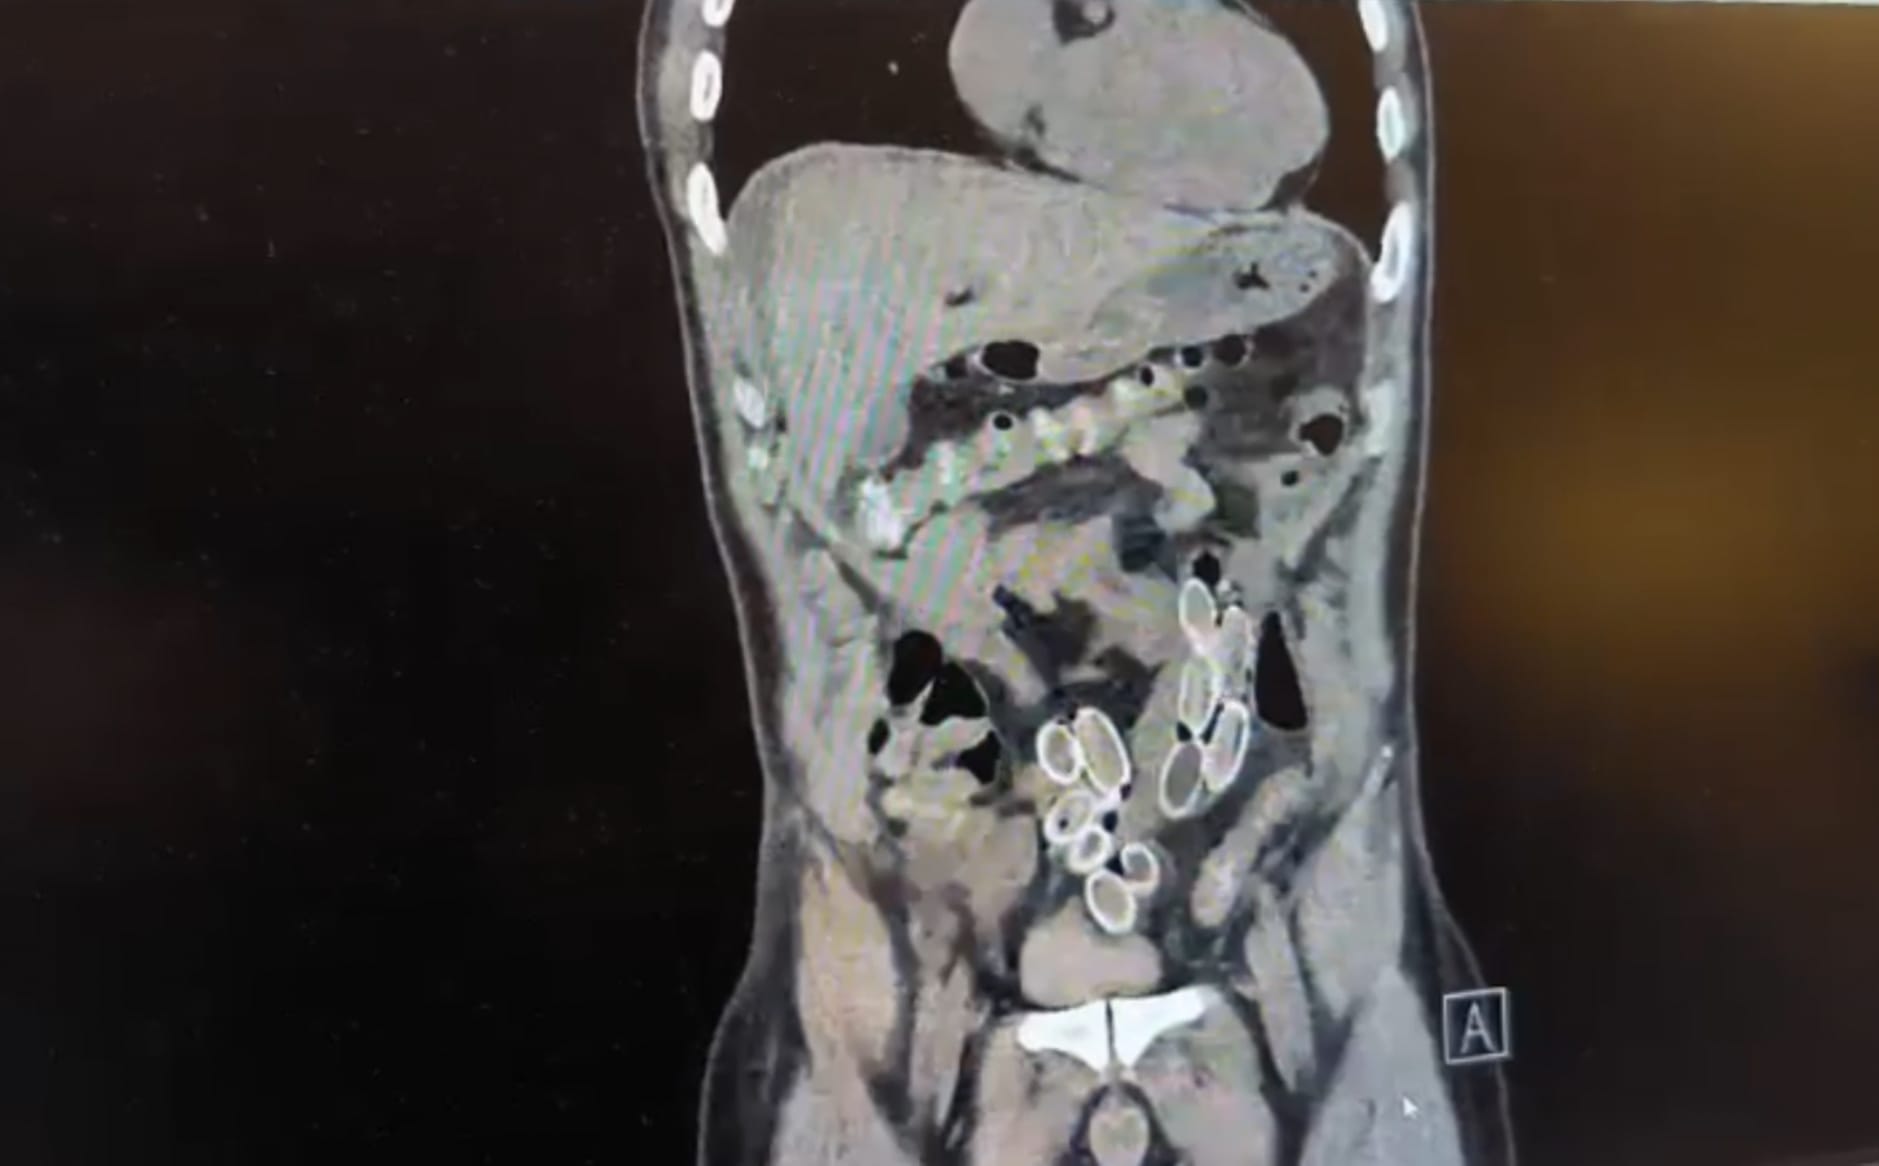

AMELİYETLA MİDE VE BAĞIRSAKLARINDAN ESRAR ÇIKARILDI!

İhbar üzerine olaya ilişkin çalışma başlatan polis ekipleri, doktorlarla görüşme gerçekleştirdi. Ameliyata alınan şahsın mide ve bağırsaklarından, toplam ağırlığı 259,7 gram olduğu öğrenilen 49 esrar macunu çıkarıldı. Şüpheliye ait 1 adet cep telefonu da hastane yetkilileri tarafından polis ekiplerine teslim edildi.